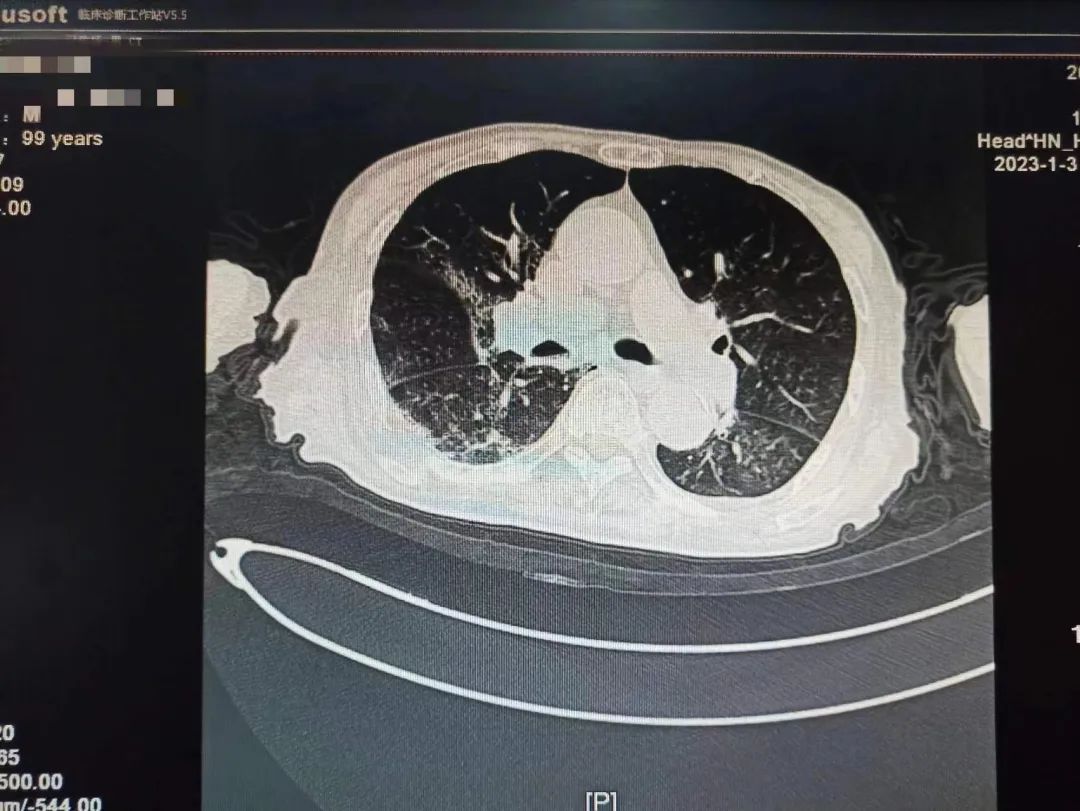

学校一附院呼吸与危重症医学科一名患者刘老爷子还差几天就到100岁生日,该患者从2022年12月22日开始持续发热,咳嗽。一开始只是以为普通的感冒,没特殊注意,后逐渐出现胸闷,乏力,精神差,在当地医院完善肺部CT,两肺大片病毒性肺炎表现,新冠核酸阳性,家属急送一附院就诊。

根据国家卫建委发布《新冠冠状病毒感染诊疗方案》最新版本指南及结合患者个体化诊疗,考虑到老人高龄,有糖尿病基础疾病,血氧饱和度偏低,属于危重症高危人群,专家团队决定给予paxlovid抗病毒治疗,激素、呼吸支持等治疗。患者住院期间一度出现嗜睡,精神极差,刘家昌主任团队时刻关注病情变化,随时调整治疗方案,并多次指出,对于这种重症肺炎患者治疗中,血氧饱和度偏低的情况,俯卧位通气具有非常重要的作用!需要“应趴尽趴”,对血氧饱和度偏低有明显改善作用!

不放弃每一个生命!全力救治!经过连续数日医护团队的精心救治,2023年1月9日,呼吸与危重症医学科医护团队再次对老人病情进行综合评估,检查显示患者肺部病灶明显吸收,精神明显好转,可以正常活动,和感染前身体体征一致。出院当天老人握着刘家昌主任的手激动的说:“多亏刘主任了,要不是你和咱们医院医护团队,我这关是闯不过去了,我还以为我过不去这一百岁坎了。”刘家昌主任对老人和家属详细交代了出院康复指导意见及注意事项。